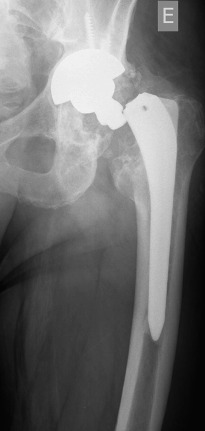

Fig. 3

Fig. 3.

Anteroposterior radiograph after the lightning strike. The fracture locates through the base of the neck.

In October 2013 (two years and one month after the revision procedure), the patient was surprised by a storm and was struck by lightning while strolling. He remained conscious and suddenly he was unable to bear weight on the left leg and a deformity on his left lower extremity was detected. His neurovascular status was stable. Plain radiographs demonstrated a displaced fracture through the base of the neck of the femoral component (Fig. 3 ). The patient underwent revision THA through a posterior iterative approach. A transfemoral osteotomy was required to extract the stem, which presented no signs of loosening. Prophylactic Dall-Miles wiring was done to prevent fractures just under the osteotomy. The selected component for the revision was a modular curve Revitan® (Zimmer, Winterthur, Switzerland) system. It was a 200 × 180 mm stem with a distal locking screw of 36 mm and a metaphysis of 75 mm with 15° of anteversion. The head was a #36 metallic. Finally, the osteotomy was fixed with four Dall-Miles cerclages (Fig. 4 ). After the surgery, the patient needed two blood transfusions due to postoperative anaemia. The postoperative course was otherwise unremarkable and the patient was allowed partial two-crutch assisted weight-bearing. The patient was discharged with an active range of motion of 75° of hip flexion and 15° of hip abduction. Three months after surgery, the radiographs demonstrated consolidation of the osteotomy. After one year, the patient is satisfied, without pain and had returned to work.